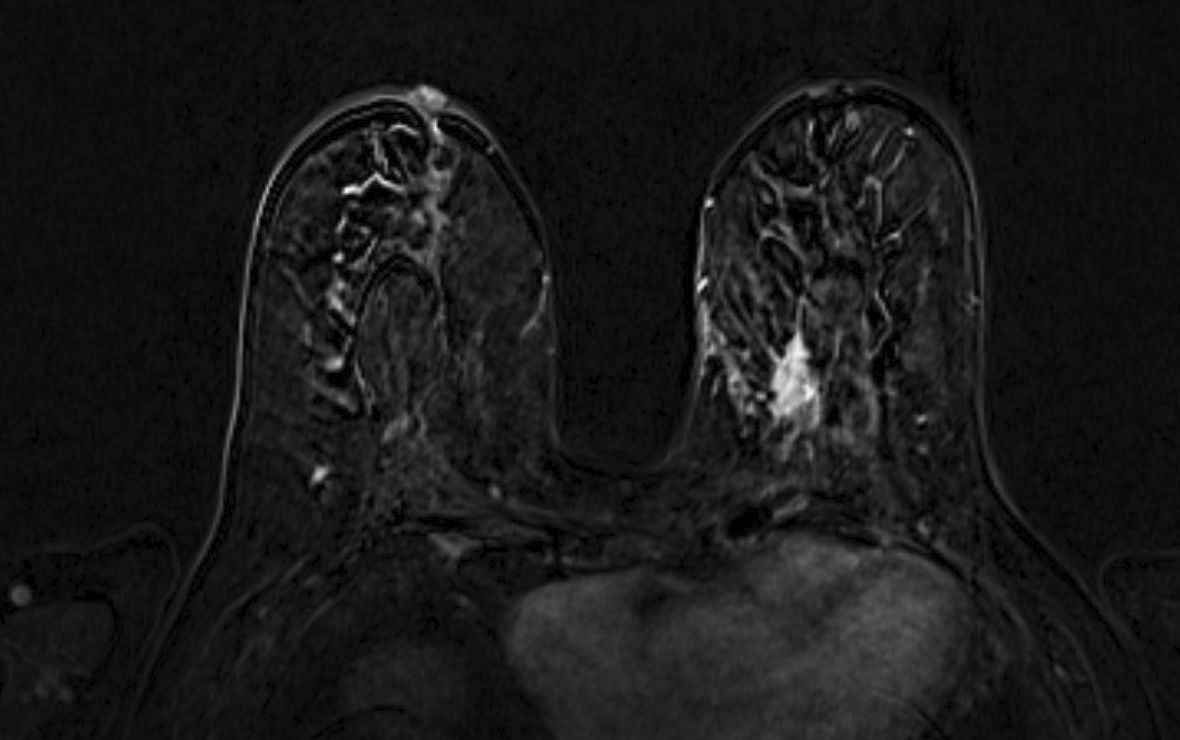

Magnetic resonance imaging (MRI) has been used as an adjunctive screening tool, mainly for women who may be at increased risk for the development of breast cancer. Example images of MRI are shown in fig. 5 with T1 contrast enhancement. MRI for screening has not been very popular in women with average risk due to concerns about the low specificity leading to additional biopsies, time and cost of technology [26]. Breast MRI sensitivity values reported in high risk screening studies range from 93% to 99%. Despite its high sensitivity, breast MRI has been reported to have variable specificity, ranging from 50% to 85% [27]. These number of sensitivity and specificity depends on the type of tumor, size of tumor, age of patient, and where it is localised.